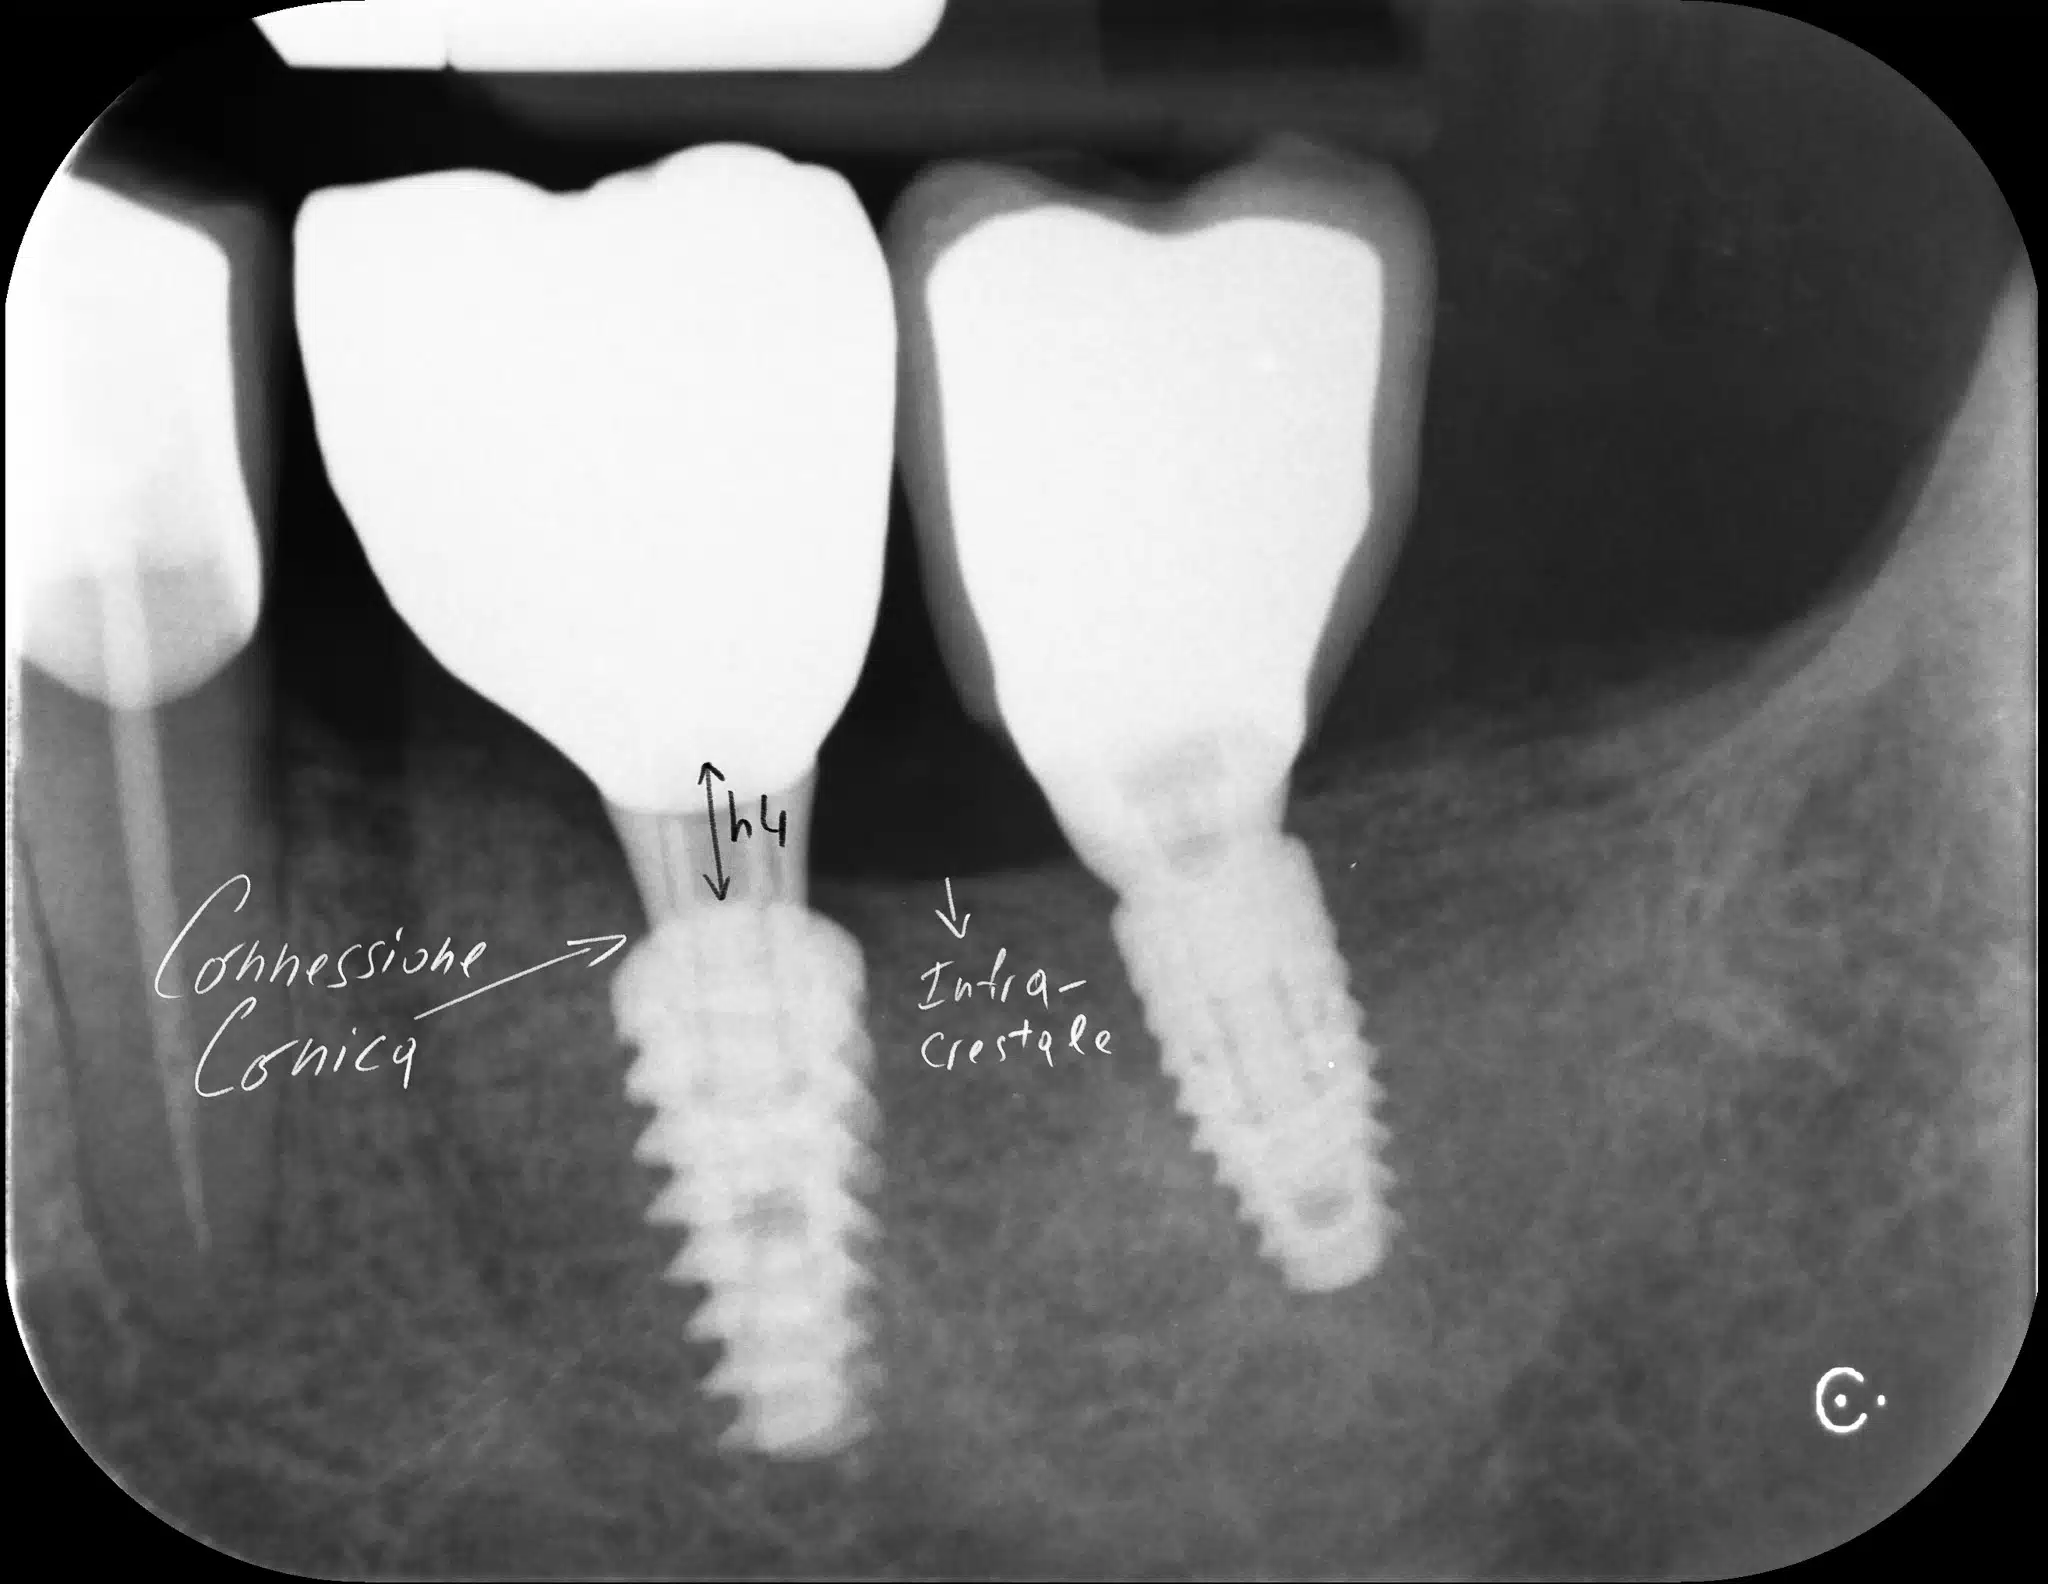

Come già scritto in precedenza, l’impianto aumenta la rigidità della mandibola, proprio come fa l’estrazione da sola seguita dal riempimento (guarigione) osseo.

L’impianto, tuttavia, introduce anche un’ulteriore variabile. Il titanio ha un modulo di elasticità (di Young) di circa 107 GPa. L’osso corticale si attesta attorno a 19 GPa. L’osso trabecolare è nell’ordine di 0.8 GPa. Il rapporto di rigidità tra titanio e osso trabecolare circostante è di oltre 100:1.

Questo rapporto è, potenzialmente, un problema. Sul lato di compressione dell’impianto, il titanio irrigidisce ulteriormente la mandibola rispetto alla situazione post-estrattiva dove l’alveolo è riempito solo da osso neoformato. Le conseguenze di questa disparità biomeccanica sono più evidenti quando l’impianto è mal posizionato: in quei casi la distribuzione delle forze diventa ancor più asimmetrica, come documentato nell’articolo Impianto Dentale Mal Posizionato: Conseguenze Biomeccaniche.

Questo è il fenomeno noto come stress shielding. L’impianto, per la sua superiori caratteristiche meccaniche rispetto all’osso circostante, “scuda” una parte dell’osso peri-implantare dalla deformazione meccanica che altrimenti lo avrebbe stimolato. Tale meccanismo, condurrebbe ad un aumentato riassorbimento dell’osso alveolare scudato.